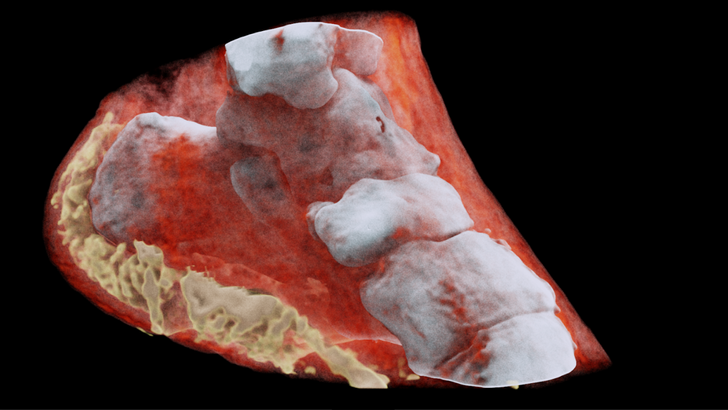

Снимок лодыжки, который сделан с помощью цветного спектрального сканера